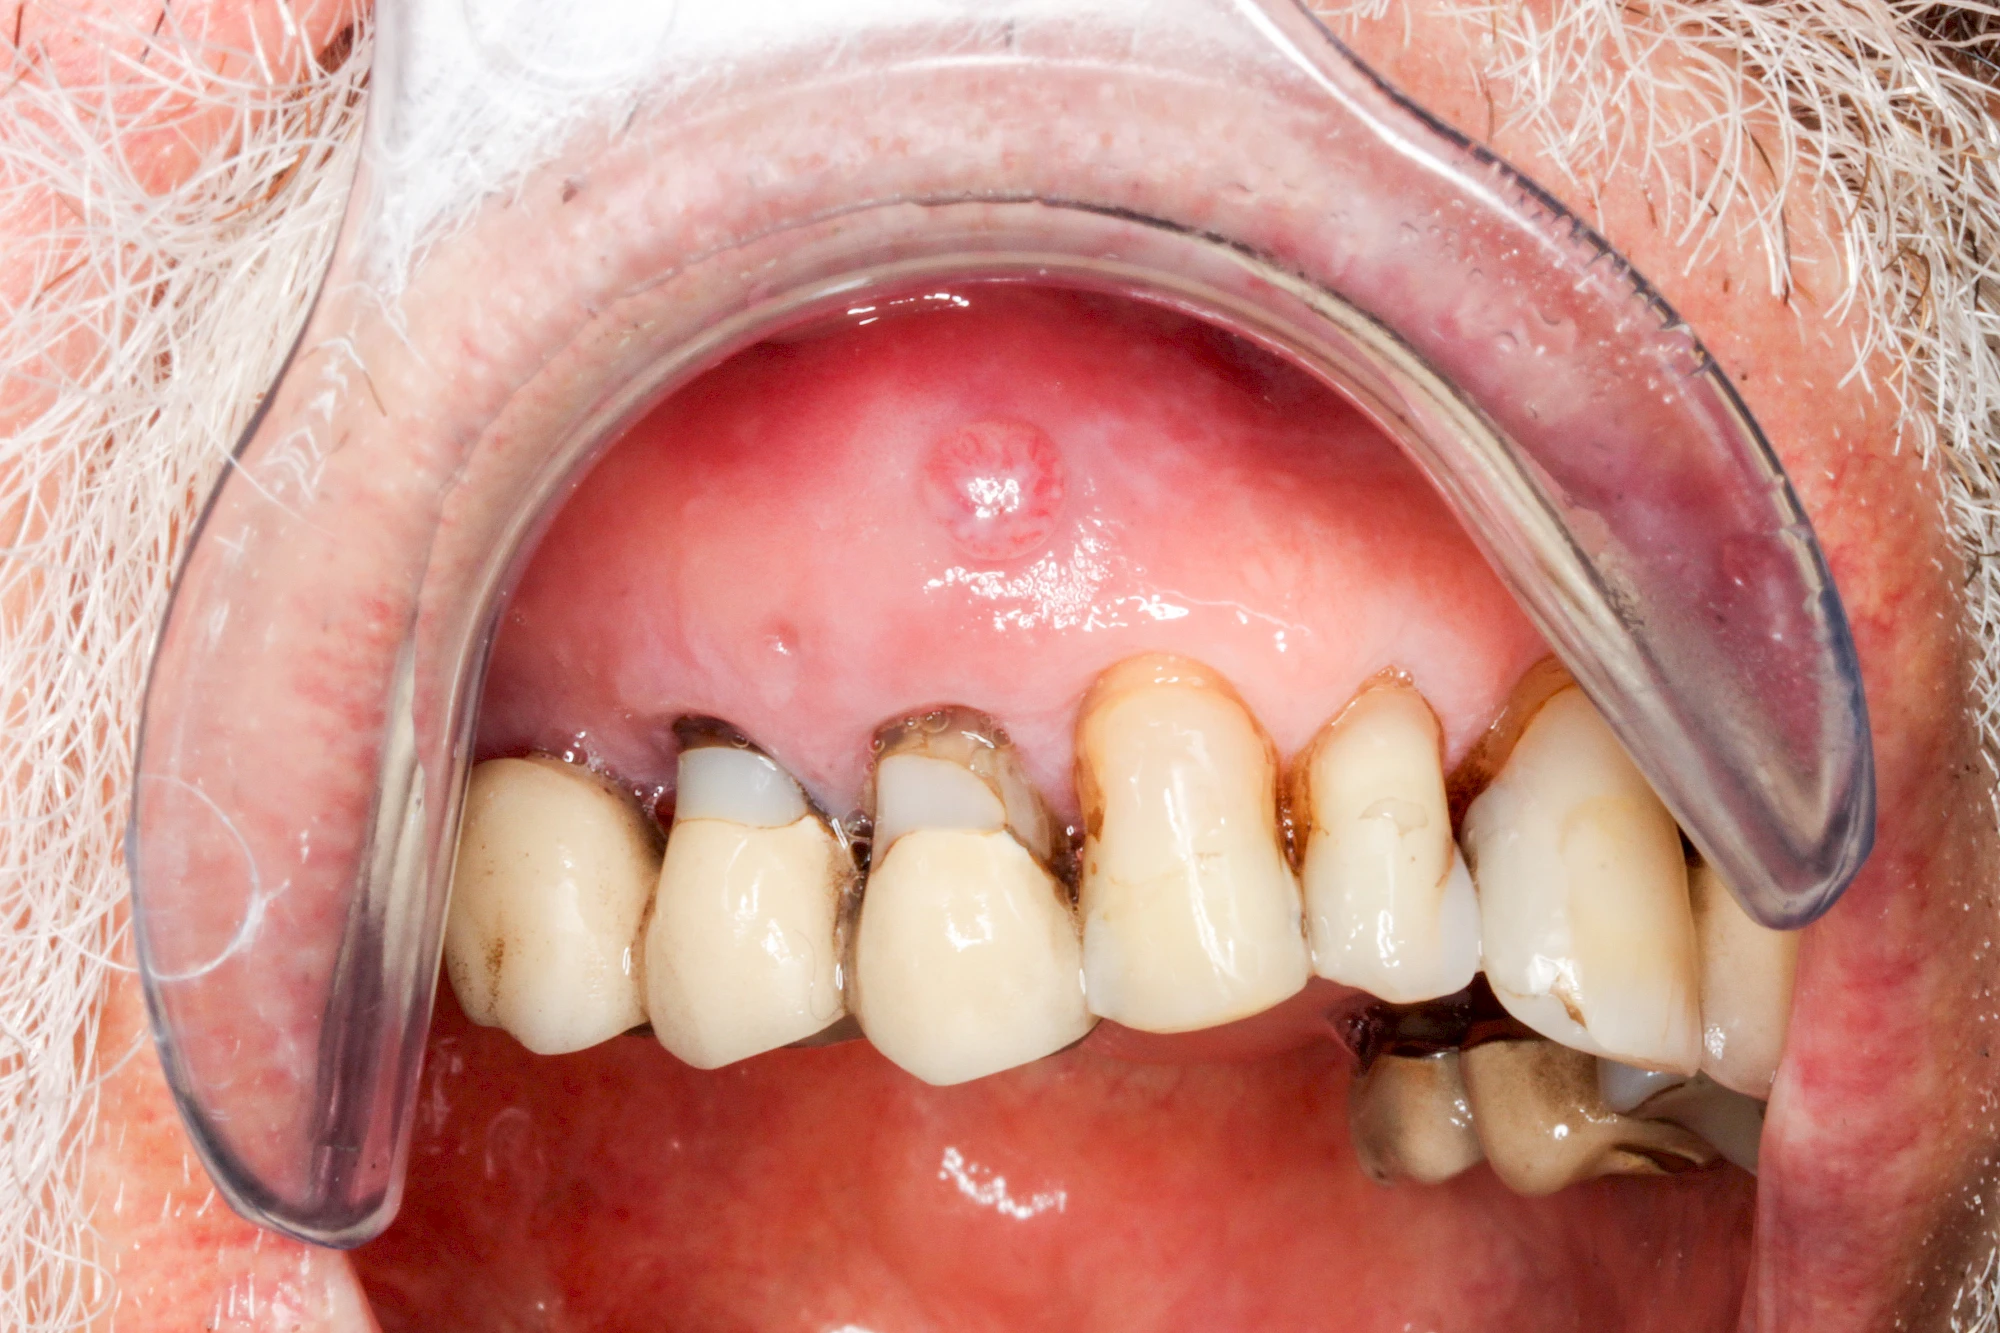

Sonderform: Fistel

Bei einer Fistel hat sich meist eine Entzündung (manchmal auch Erreger selbst) z. B. aufgrund von Karies oder aufgrund eines Unfalls über den Zahnnerv und die Wurzelspitze (Apex) in den umliegenden Knochen ausgebreitet (apikale Parodontitis) und schnell einen Weg durch den umgebenden Knochen und die aufliegende Schleimhaut in die Mundhöhle gebahnt.

Fisteln sind in der Regel nicht schmerzhaft und fallen häufig als kleine Öffnung weiter entfernt vom Zahnfleisch nahe der Umschlagfalte auf. Aus der Fistelöffnung entleert sich spontan gelbliches Sekret (Eiter) oder es lässt sich mit dem Finger ausstreichen. Manchmal beschreiben die betroffenen Menschen immer wieder einen komischen Geschmack im Mund.

Im fortgeschrittenen Stadium kann die Schleimhaut sich weiter zurückgezogen haben und die Wurzelspitze sichtbar sein. In der Regel treten bei Fisteln keine Schwellungen auf, weil sich die Entzündung nicht im Gewebe ausbreitet.